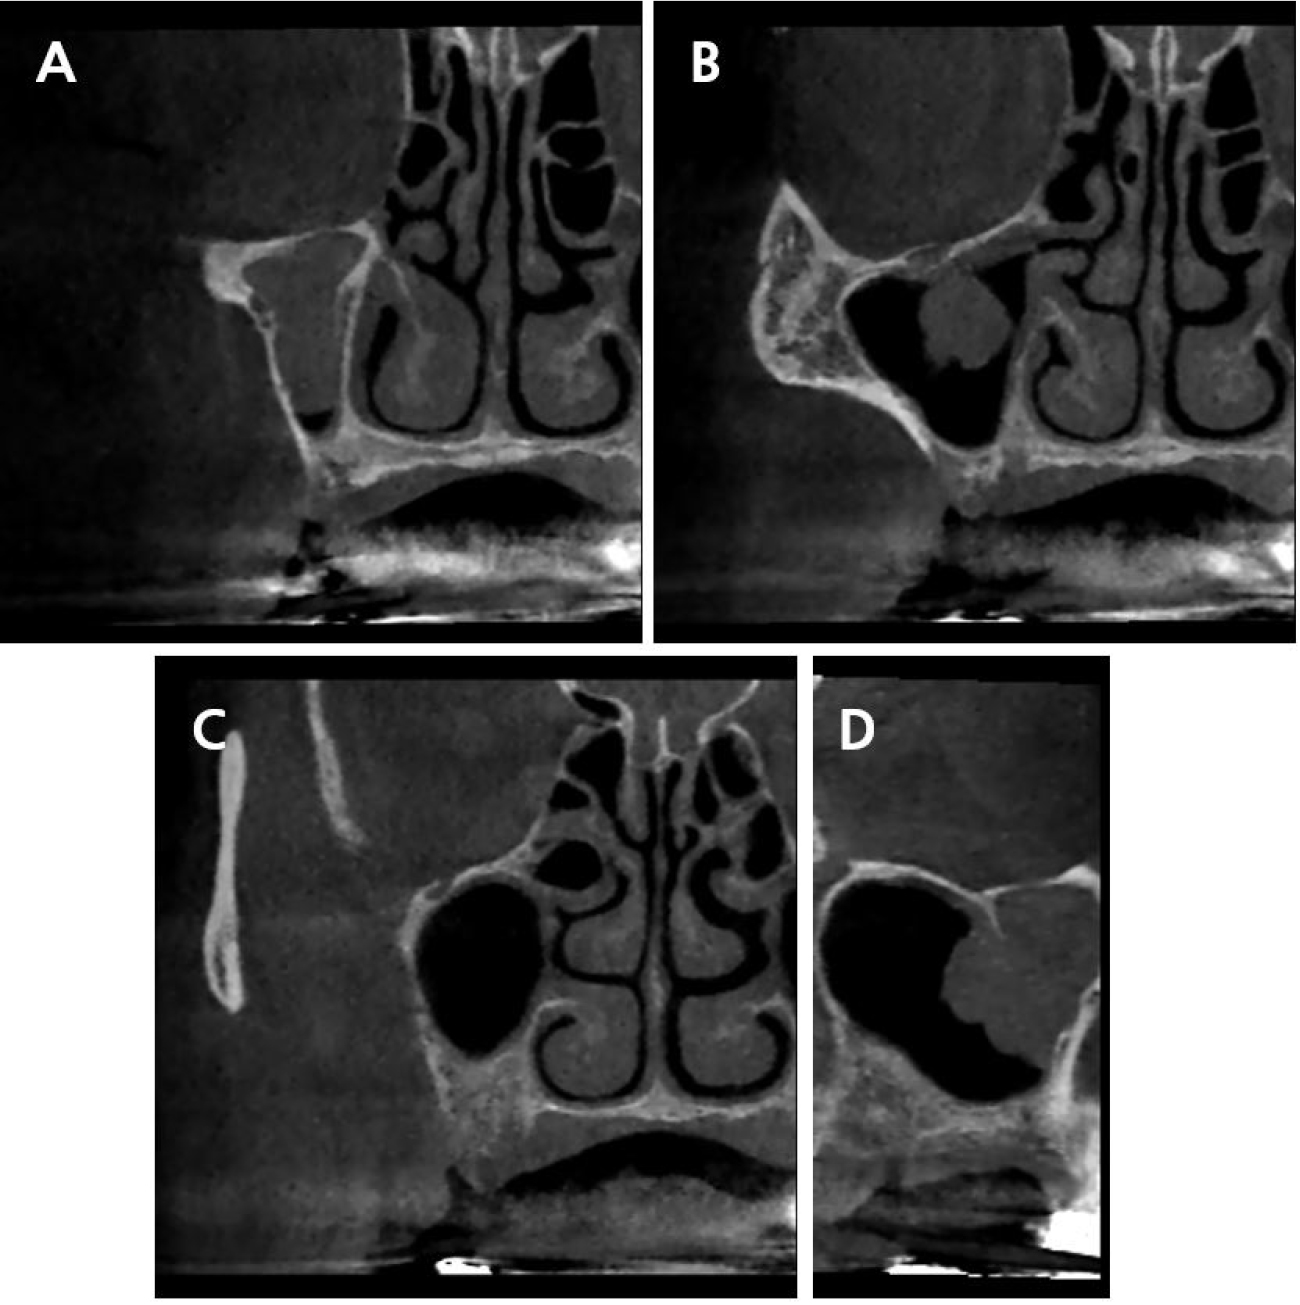

The CBCT scans revealed radiolucency indicative of a tumor near the sinus ostium, impeding normal sinus drainage, with irregular thickening of the Schneiderian membrane (Fig. 1). Dome-shaped and cyst-like opacity of the antral pseudocyst is a frequent finding in the maxillary sinus, and it is not a contraindication for sinus augmentation.13 However, the irregular contour observed on the CBCT appeared different from that of an antral pseudocyst. Although there was no facial discomfort or nasal congestion, the patient was referred to an otolaryngologist before sinus augmentation.

Fig. 1.

Cone-beam computed tomographic images of the pathologic findings of the right maxillary sinus suggestive of inverted papilloma. (A) Cross-sectional view of the maxillary second premolar region, (B) Cross-sectional view of the maxillary first molar region, (C) Cross-sectional view of the maxillary second molar region, (D) Sagittal view.